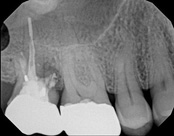

The patient presented with mild pain, a cavity, and a broken filling was evident. After performing diagnostic testing, the diagnosis was: irreversible pulpitis, symptomatic periradicular periodontitis. Root canal therapy was done and the tooth healed well and is still functioning.